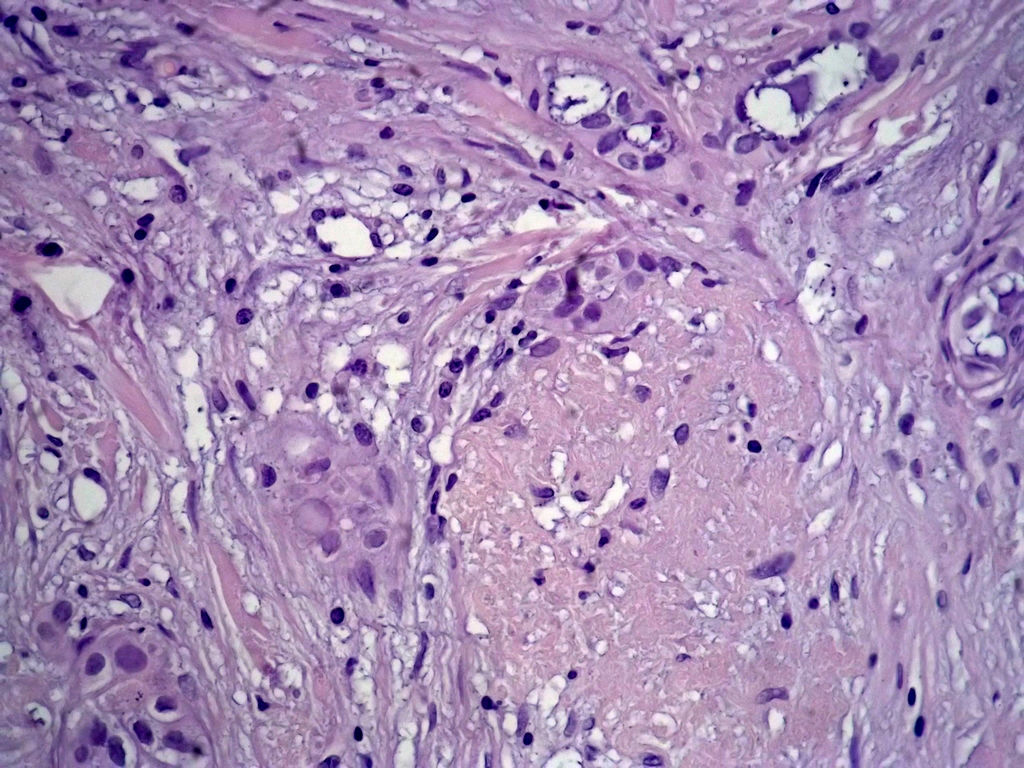

今天的一例术中冰冻。女,49岁,乳腺肿块。人气不旺,换个标题

腺病?癌?其他?(12楼常规,24楼免疫组化及会诊结果)图1

标签:浸润性导管癌 分泌癌 硬化性腺病

乳腺分泌型癌

多谢强版主,这可是俺亲自全程操作的一张片子,俺的一点小经验是“组织要干”,“冷冻要快”,这个病例有点考验俺的神经,发上来听听高手们的意见。大体是乳腺组织一块,切面见一质硬结节,直径2cm,边界欠清,切面灰白色。强版别光夸片子漂亮啊,留下你的高见才放行

导管是乎可见双层上皮,部分上皮增生并有一定异型,考虑硬化性腺病,待石蜡。

导管可见双层上皮,部分上皮增生并有一定异型,考虑硬化性腺病

腺体与腺体之间的对比差异太大,不放心,不除外是癌,如果是我的病例,再次取材冰冻

占楼传常规1-11为冰对。